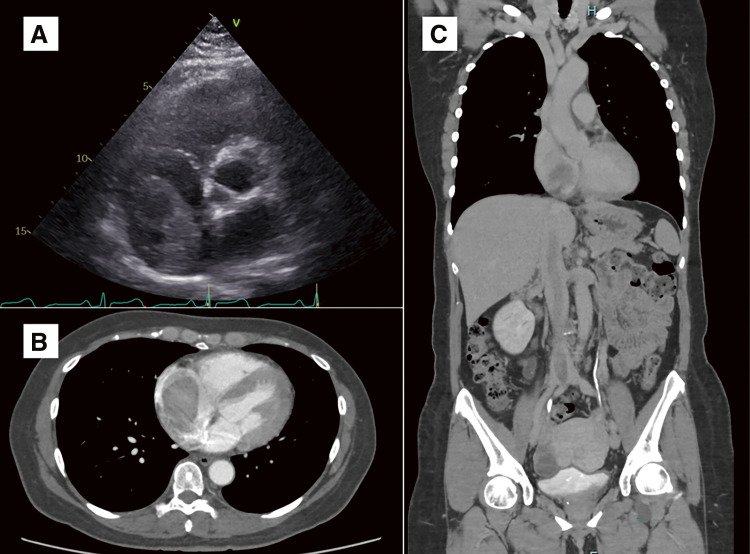

静脉平滑肌瘤病(IVL)仍然很少报道,完全切除肿瘤是推荐的治疗方法。在此,我们提出了一个全面的审查的情况下,52岁的妇女谁遭受复发性晕厥发作由于IVL心内延伸到右心房。先行肿瘤部分切除及术后激素治疗。然而,术后6个月随访的计算机断层扫描显示IVL有增大的趋势,因此进行了完全切除。在本文中,我们想强调的是,部分切除后激素治疗是不够的IVL,应选择完全切除。

Intravenous leiomyomatosis (IVL) remains scarcely reported, and complete tumor resection is the recommended treatment. Herein, we present a comprehensive review of the case of a 52-year-old woman who suffered from recurrent syncope episodes due to IVL with intracardiac extension to the right atrium. Partial tumor resection and postoperative hormone therapy were conducted first. However, the 6-month postoperative follow-up computed tomography scan revealed a tendency for the IVL to increase in size, and complete resection was conducted. In this article, we would like to emphasize that partial resection followed by hormone therapy is insufficient for IVL, and complete resection should be chosen.